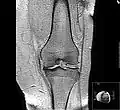

Diagnosis is made with reasonable certainty based on history and clinical examination.[52][53] X-rays may confirm the diagnosis. The typical changes seen on X-ray include: joint space narrowing, subchondral sclerosis (increased bone formation around the joint), subchondral cyst formation, and osteophytes.[54] Plain films may not correlate with the findings on physical examination or with the degree of pain.[55]